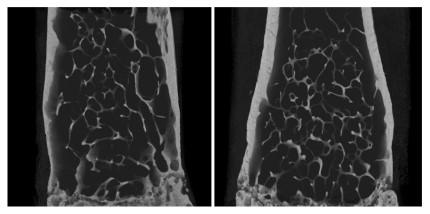

On the left is a femur from a normal mouse and on the right is a genetically engineered mouse with an alteration in a gene that constitutionally increases the density and strength of the bones as evidenced by the thickness of the bony cortex on the outside of the femur. Credit: Emma Wade

Professor Stephen Robertson from the Dunedin School of Medicine and Dr Sujay Ithychanda from the Lerner Research Institute in the United States have discovered mutations in two different human genes that result in excessive bone density, or hyperostosis, where bones are denser and stronger than normal. Their Marsden-funded project will investigate whether the proteins encoded by these genes represent the long-sought sensor of mechanical stress in bone-forming cells.